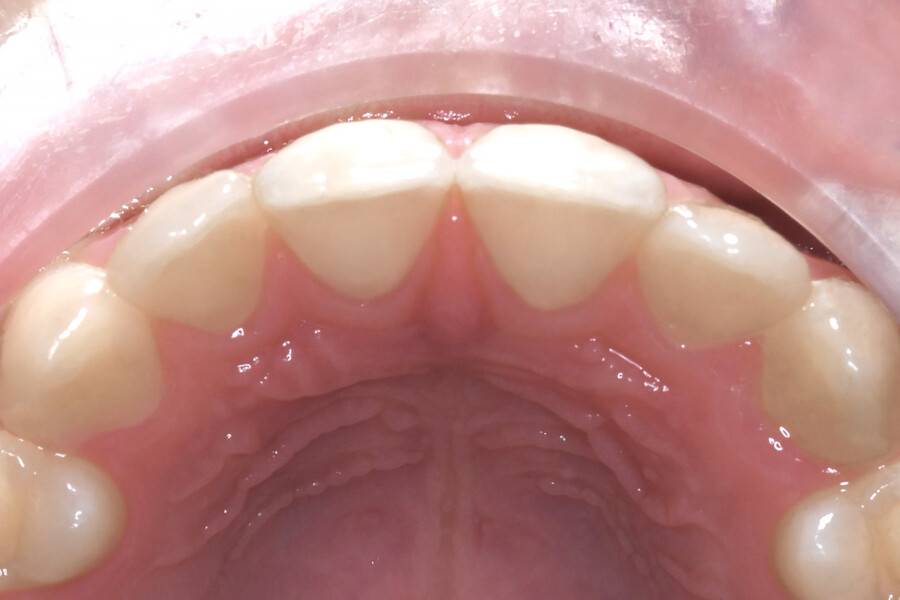

8 лет, девочка, жалобы на неправильный прикус и дефицит места зубам

Исправление прикуса

2,5 года

Выполнено лечение с помощью LM-активатора на ночь